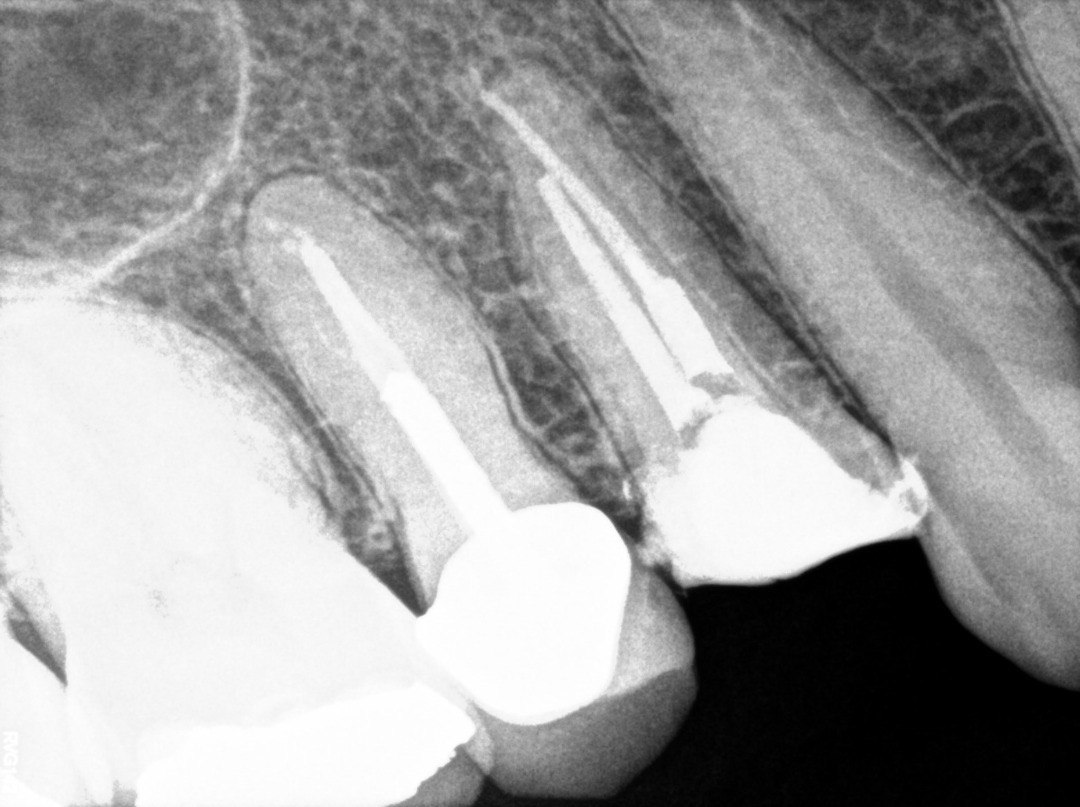

1. Evaluate the root canal treatment of tooth # 2.5?